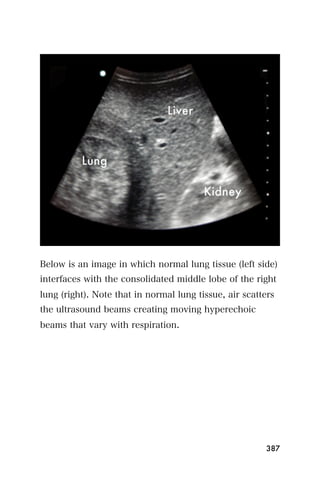

Figure 5. Parasternal long axis view showing a pericardial effusion (*)

The effusion will be seen between the heart and the

pericardium ̶ a thin bright white line on

echocardiography. Please see the corresponding

narrated lecture for video of pericardial effusion.

Pericardial effusions can be of different sizes. They can

be loculated (around a portion of the heart) or

circumferential (around the entire heart). Sometimes

they are completely echo-lucent (black), and sometimes

gray-colored stranding may be visualized, as seen in the

pericardial effusion from tuberculosis in Figure 6.